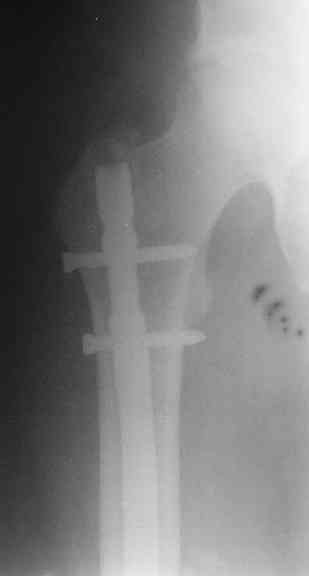

> денамизация - февраль 2006. ( 3 и 4 снимки) на сегодняшний день (снимок 5) беспокоит боли в тбс...

Однозначно: удалить, рассверлить, перештифтовать более толстым гвоздем. ЭТОТ 9 мм будет? Возьмите 12-14.

Дистально обязательно два винта! Проксимально можно один динамический. Больной будет счастлив на следующий же день!

Согласен, что закрытый реостеосинтез с рассверливанием и коррекцией оси - это то, что надо. Мы бы ввели в центральный отломок статических 2-3 винта, и один динамический винт в дистальном отломке.

Данный стержень у данного пациента позволяет смещаться отломкам по длине, ширине, на варус и вокруг вертикальной оси.